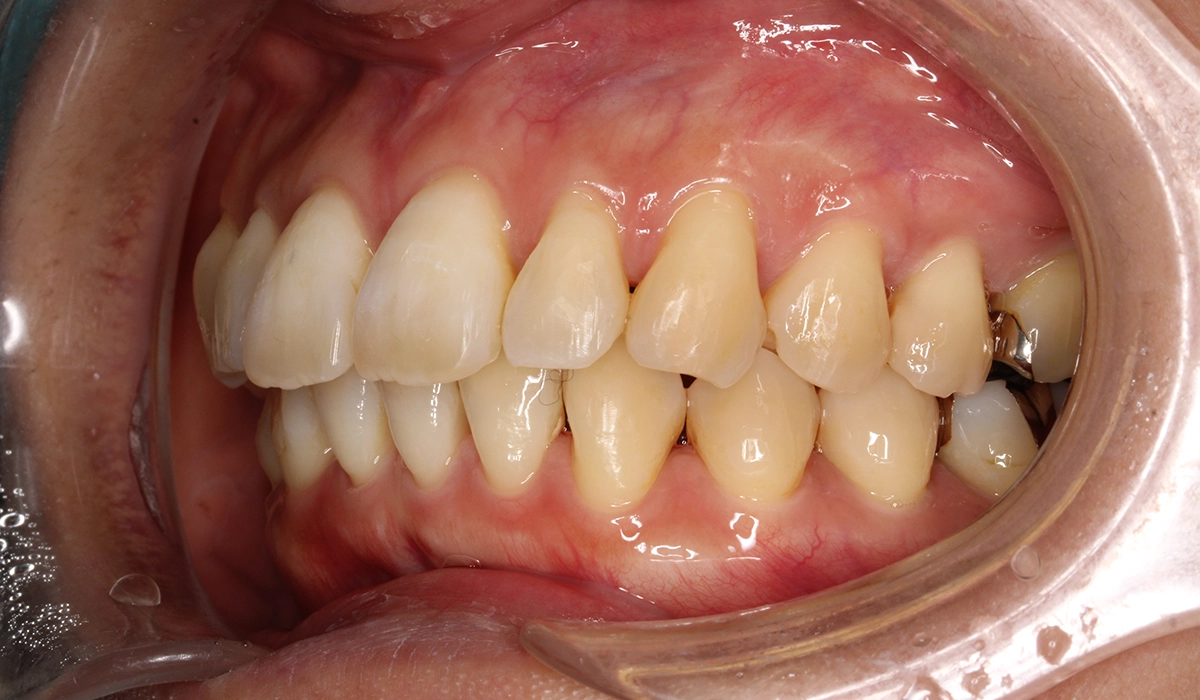

術前:正面

術後:正面